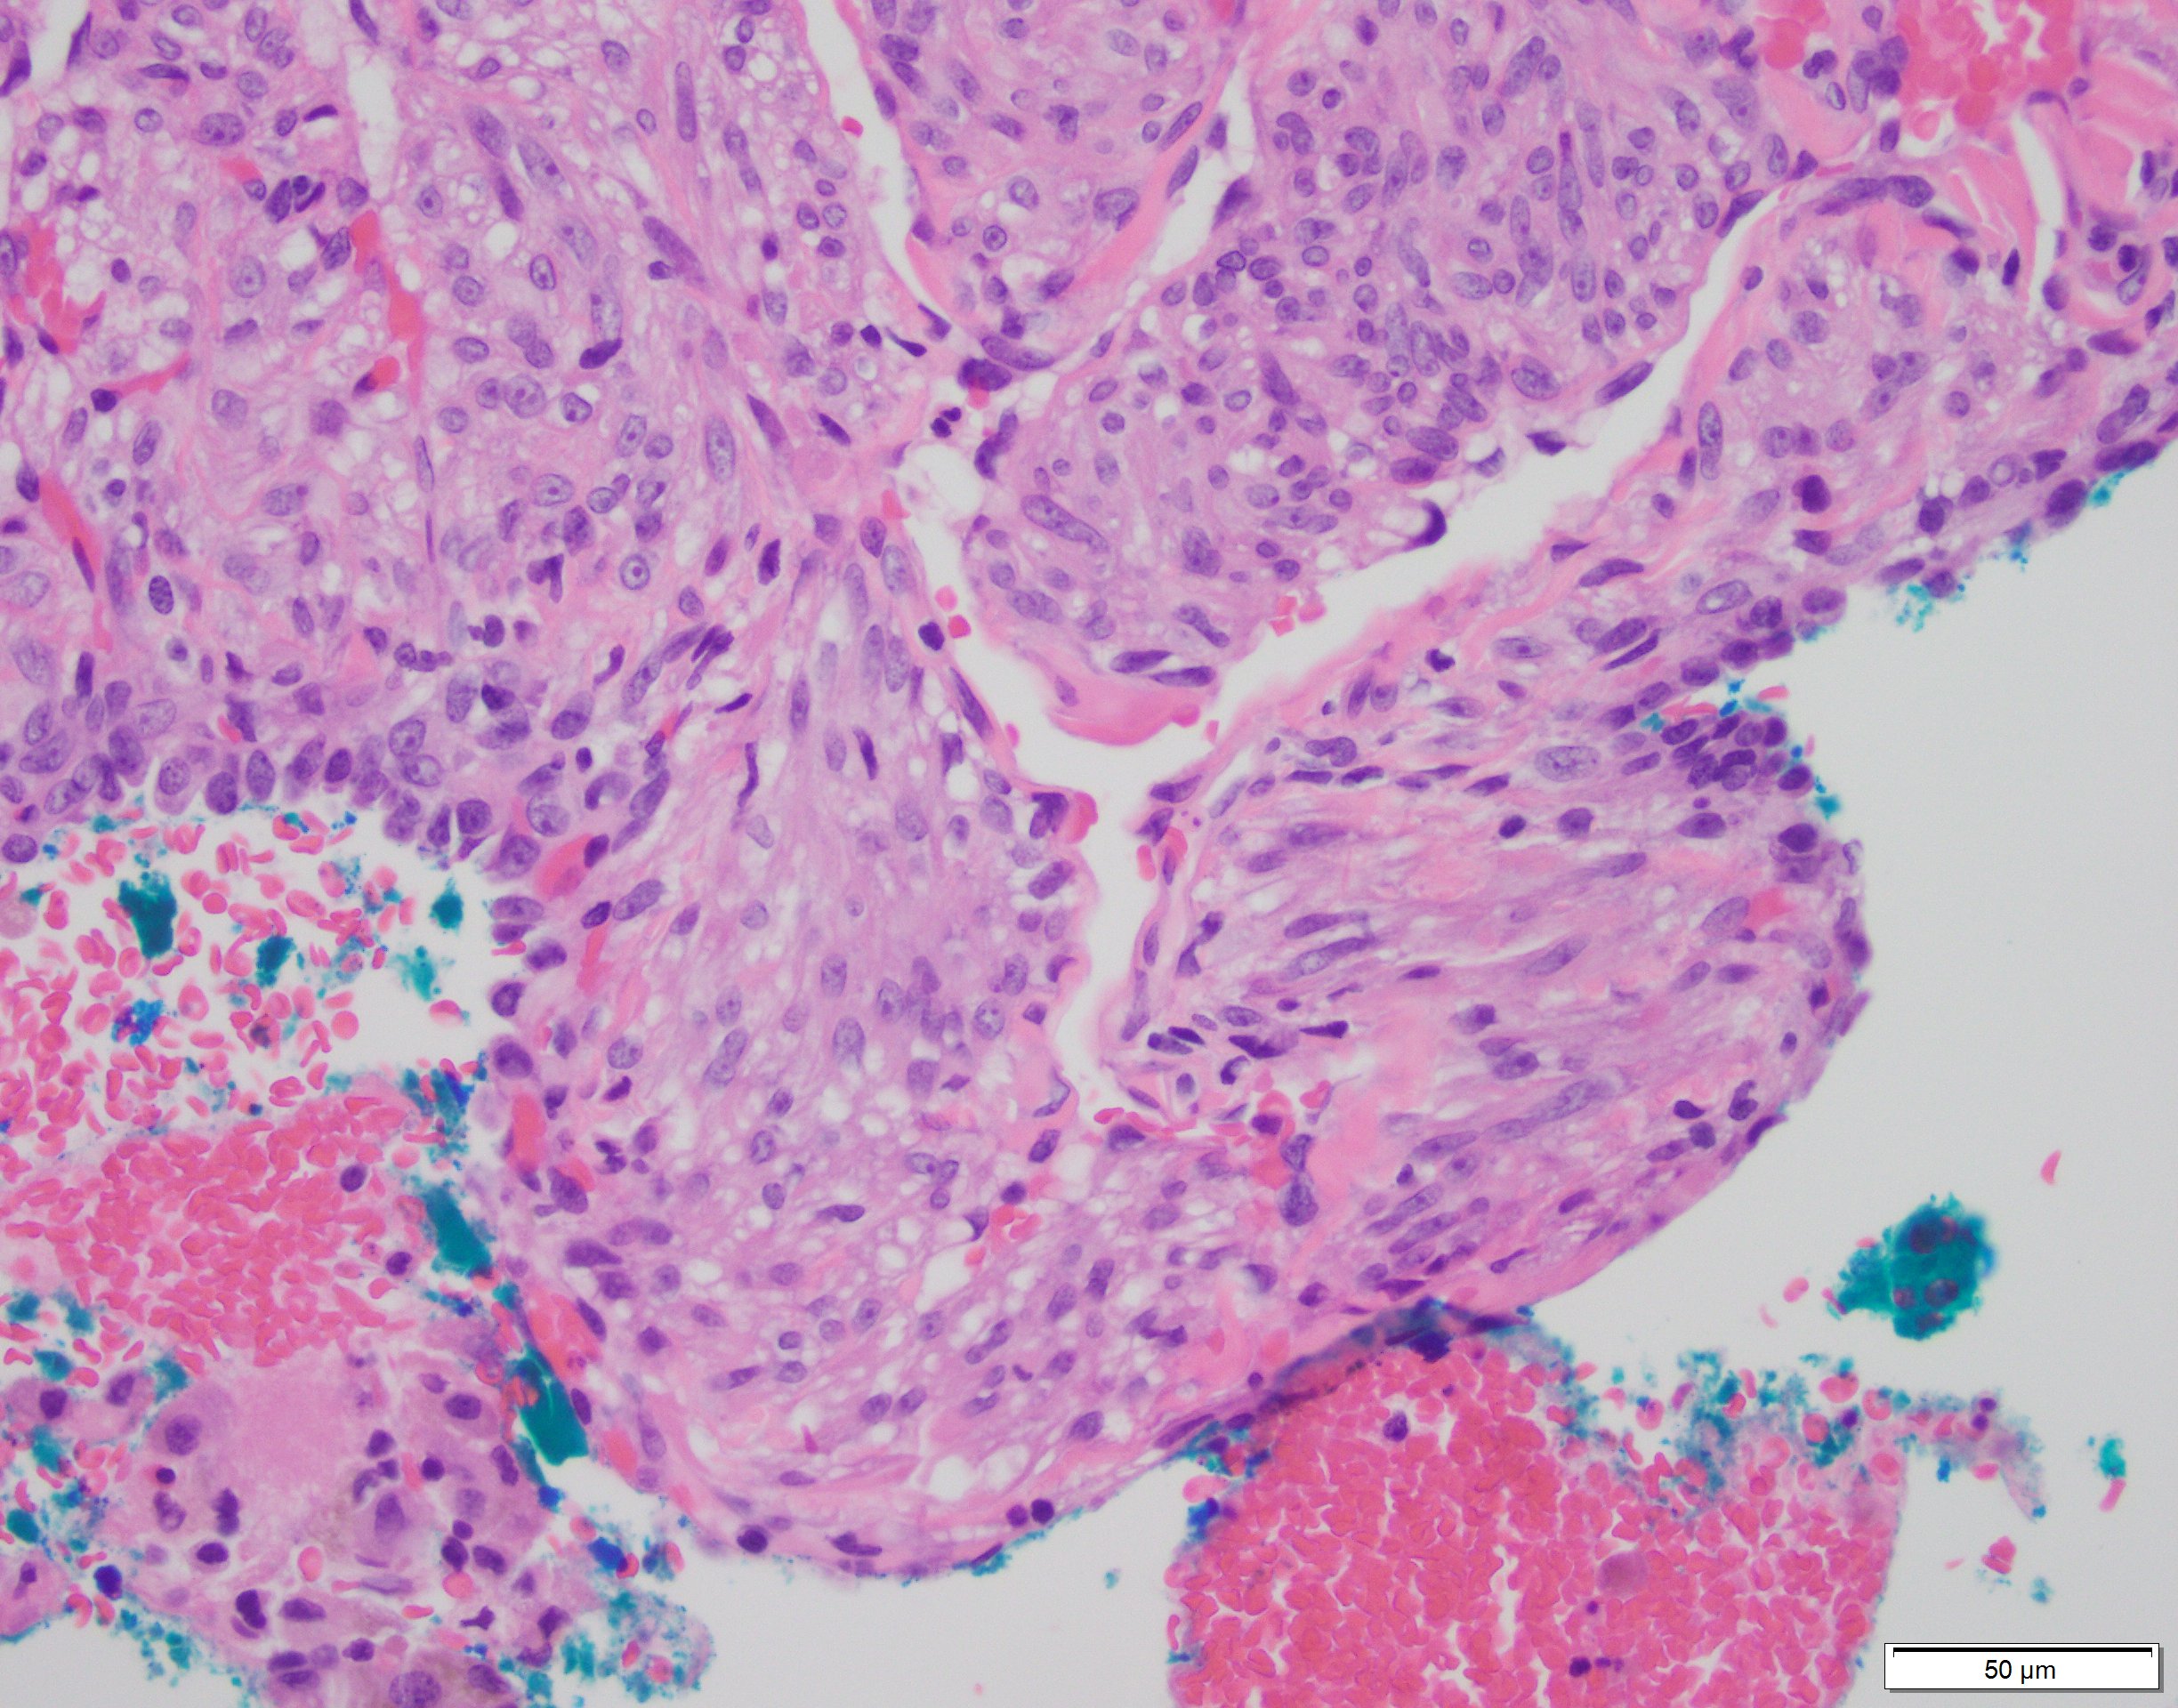

Low power view shows cysts lined by a thickened wall and random areas of expanded interstitium. Higher power shows these expanded areas occupied by bland, short, plump, myoid spindly cells, with eosinophilic or cleared cytoplasm. The so-called “LAM” cells are positive for HMB45, and also SMA, ER, and PR [2].

LAM is a rare non-neoplastic interstitial lung disease, almost exclusively seen in premenopausal women and has a disease association with tuberous sclerosis in a subset. The tumor is characterized by a bland spindled or epithelioid proliferation, belonging to the so-called PEComa family of tumors, named aptly for Perivascular Epithelioid Cell differentiation. The PEComa family of related mesenchymal neoplasms include angiomyolipoma, lymphangiomyomatosis, and clear cell "sugar" tumor of the lung. As a family, these tumors characteristically share immunoreactivity for melanocytic (HMB45 or melanA) and smooth muscle markers (SMA and/or desmin)[1].